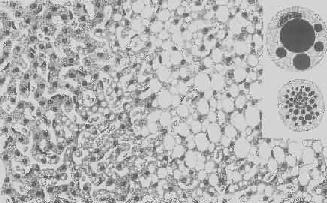

肝细胞脂肪变性

图1-18 肝细胞脂肪变性

肝细胞胞浆内出现大小不等的脂肪空泡;右上角为饿酸染色的脂肪细胞, 脂滴染成黑色